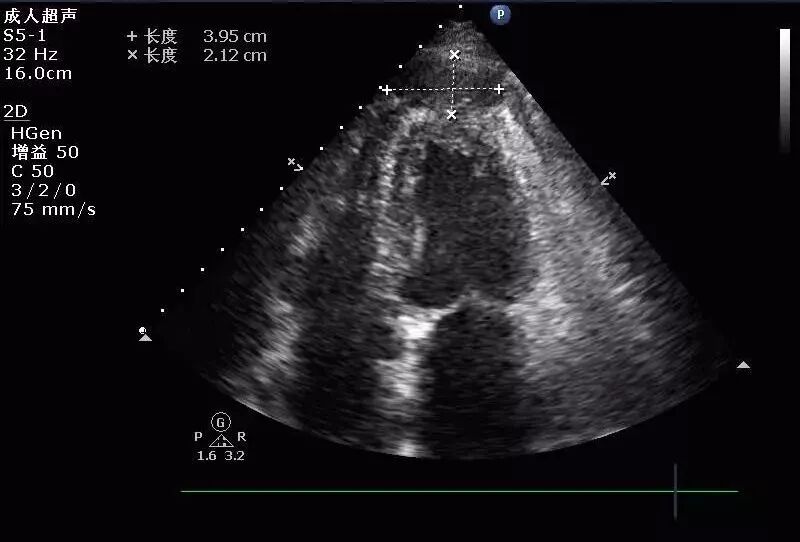

(图5)

图5: 2017年8月30日复查经胸超声心动图提示:左室靠近心尖处血肿形成。少量心包积液。左室靠近心尖处外壁可见一低回声包块,大小约40mmx21mm,边界尚清。

(图6)

图6 :心包腔见液性暗区,右室前壁4mm,左室后壁5mm。